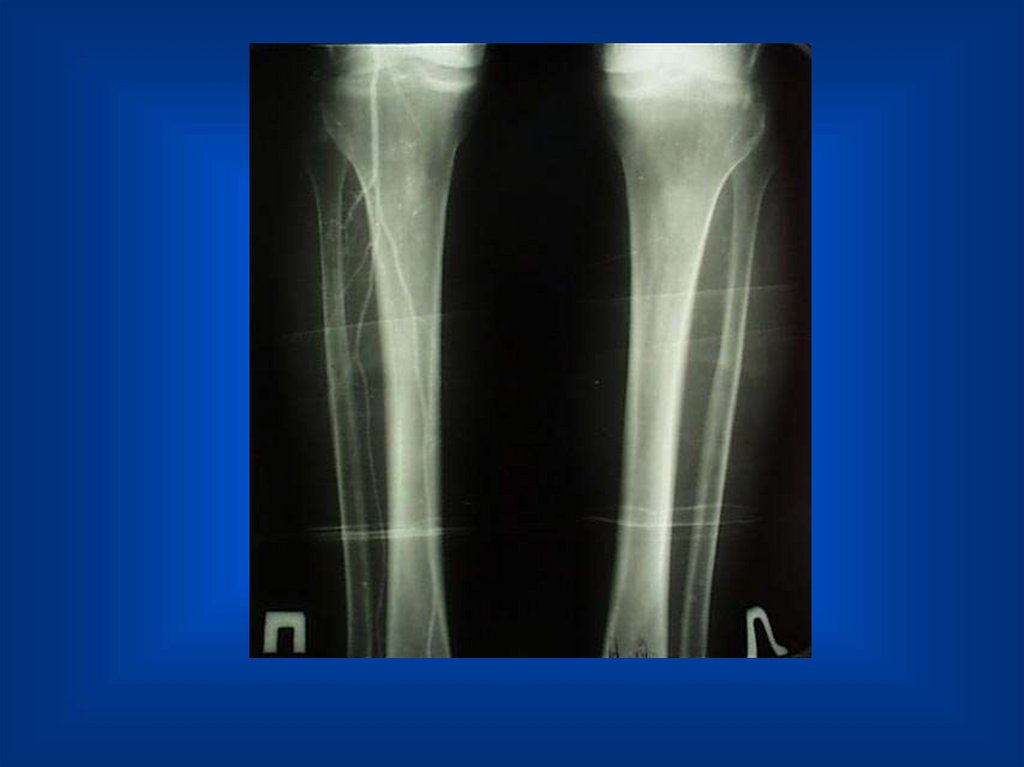

Окклюзия артерий голени

Окклюзия артерий обеих голеней